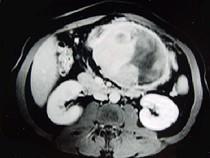

问题 男,36岁,腹胀、消化不良、消瘦、中上腹痛,影像检查如下图,最可能的诊断是()

选项 A.胃间质肉瘤并肝转移 B.胃间质瘤并原发性肝癌 C.内胚窦瘤肝转移 D.胃淋巴瘤伴原发性肝癌 E.胃间质瘤并肝血管瘤

答案 A